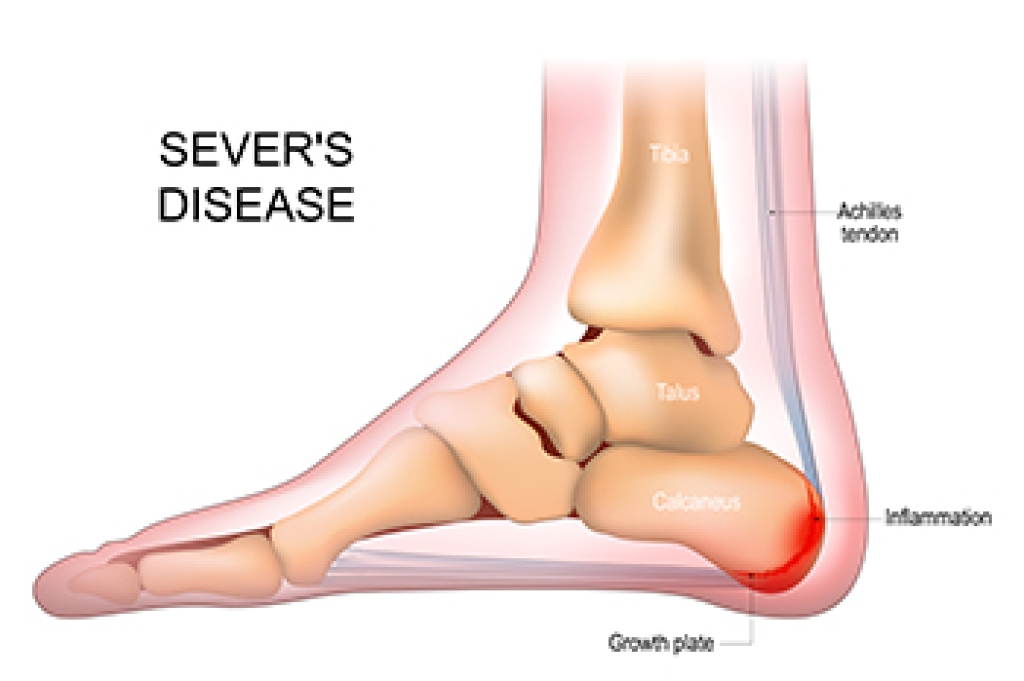

Ankle pain is any condition that causes pain in the ankle. Due to the fact that the ankle consists of tendons, muscles, bones, and ligaments, ankle pain can come from a number of different conditions.

- Achilles tendinitis

Symptoms of ankle injury vary based upon the condition. Pain may include general pain and discomfort, swelling, aching, redness, bruising, burning or stabbing sensations, and/or loss of sensation.

Due to the wide variety of potential causes of ankle pain, podiatrists will utilize a number of different methods to properly diagnose ankle pain. This can include asking for personal and family medical histories and of any recent injuries. Further diagnosis may include sensation tests, a physical examination, and potentially x-rays or other imaging tests.